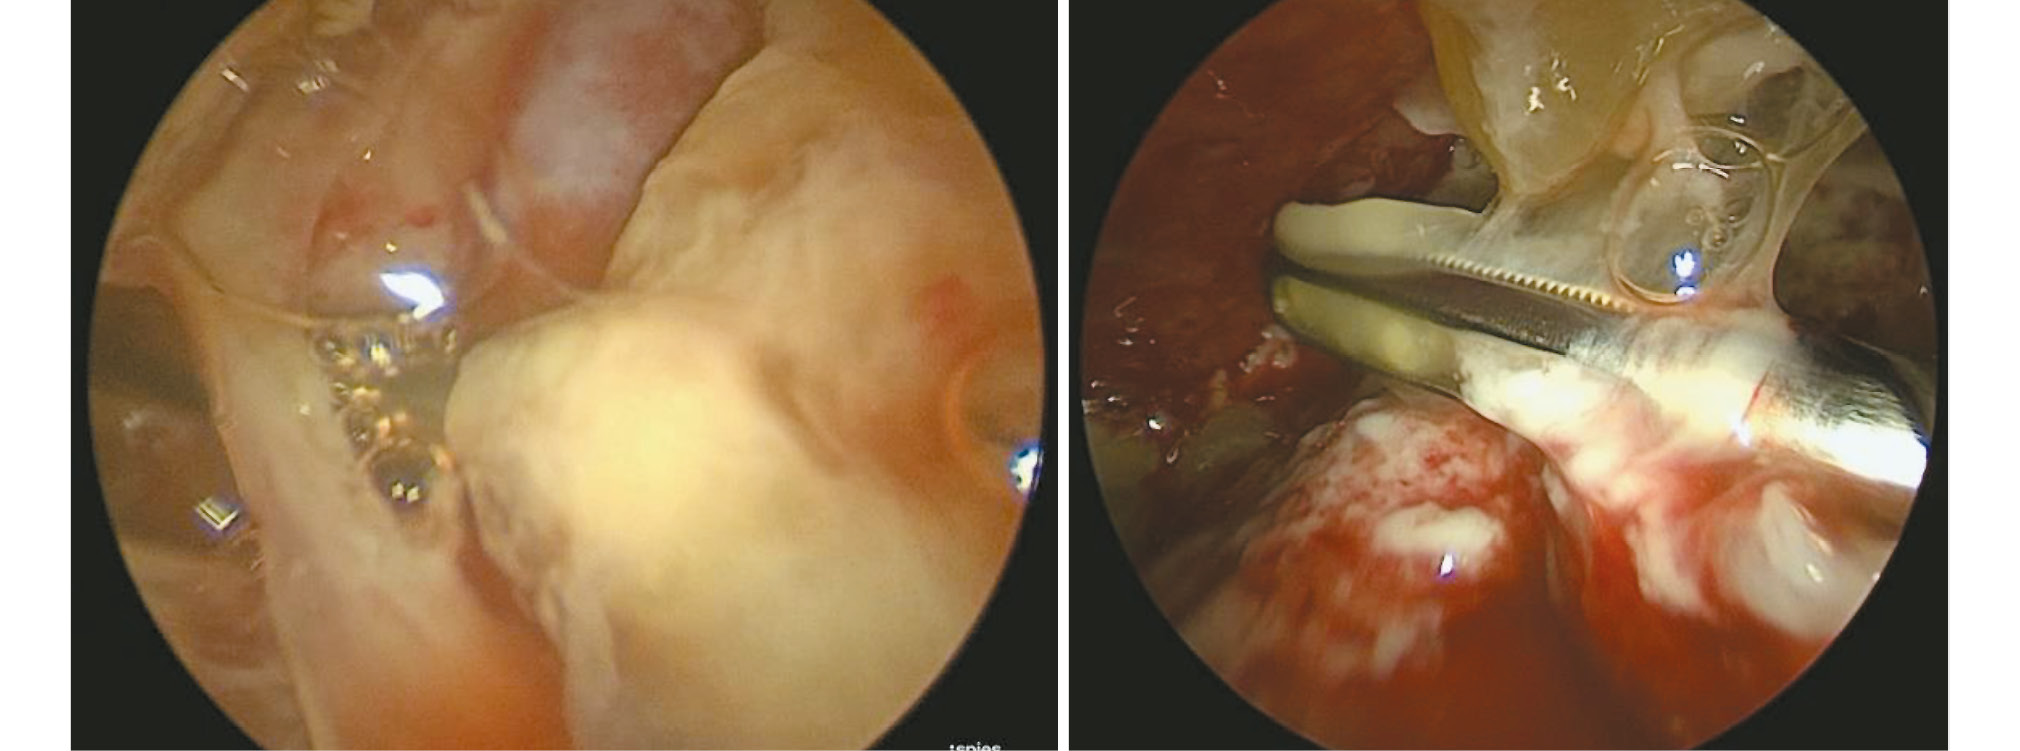

Оперативное вмешательство в обеих группах заключалось в обеспечении доступа в плевральную полость: сначала устанавливали оптический торакопорт в 5 межреберье по лопаточной линии, затем под визуальным контролем устанавливали 2 рабочих торакопорта — в 6–7 межреберье по передней подмышечной линии и в 7 межреберье по задней подмышечной или лопаточной линии. При наличии дренажного канала оптический торакопорт устанавливали вместо дренажа — 6 (23,1%) больных. Затем проводили ревизию плевральной полости с механическим разделением плевральных спаек и шварт (рис. 1). После эвакуации гноя и основной массы фибрина проводили УЗК плевральной полости и лёгкого, последовательно используя все имеющиеся доступы. Фибриновые массы по завершении этапа кавитации эвакуировали электроотсосом. Кавитацию проводили ультразвуковым аппаратом «SONOCA-190» (Soring, Германия) с частотой 25 кГц. Продолжительность и интенсивность режима воздействия определялись стадией плеврита, физическими характеристиками фибриновых плёнок, выраженностью деструктивных изменений в лёгочной ткани и возрастом пациента. В среднем время экспозиция УЗНЧ составляла 5–7 мин в режиме 40–60%. Заканчивали операцию установкой двух дренажей из нижних точек диафрагмальных синусов через рабочие доступы по направлению к верхней апертуре грудной клетки для оптимальной эвакуации плеврального выпота. Случаи внутрилёгочных абсцессотомий завершали постановкой дополнительного спирального дренажа в полость абсцесса.

Рис. 1. Интраоперационная картина ревизии плевральной полости с последующим механическим разделением плевральных спаек и шварт.

Fig. 1. Intraoperative picture of pleural cavity revision with subsequent mechanical separation of pleural adhesions and moorings.